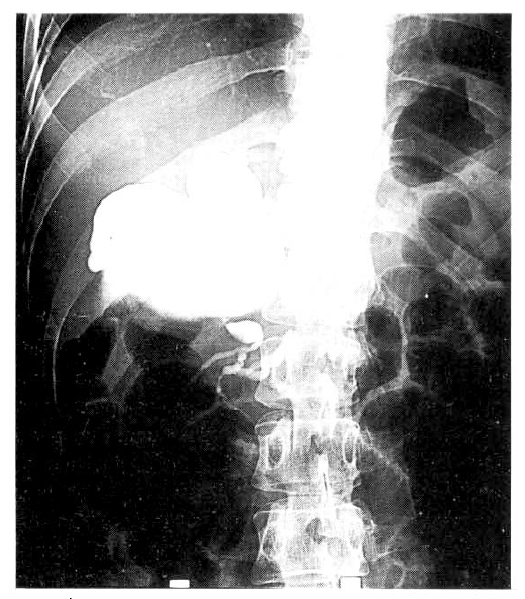

A 29-year-old nulliparous woman at 32nd week gestation began experiencing epigastric burning and back pain associated with nausea and vomiting. She had no significant gynecological, past medical history. She denied any drug ingestion, foreign travel or recent contact with infectious disease and there was no history of fatty food intolerance or long standing indigestion. On examination, the patient was afebrile with normal vital signs. She was not anemic or jaundiced. Abdominal palpation confirmed tenderness in the epigastrium. Fetal movements were felt and the uterus was of an appropriate size for gestational age. The full blood count showed leukocytosis of 12000/mm3 and serum amylase 174U/L (normal 30–110U/L) and lipase 1297U/L (normal 23–300 U/L) were elevated. Laboratory values revealed total bilirubin of 1.2mg/dl, direct bilirubin 0.7mg/dl, alkaline phosphatase 189IU/L, AST 71U/L, ALT 73U/L. The hepatitis screens were negative. All other laboratory values were within normal limits. A diagnosis of acute pancreatitis was made. Ultrasonography of the abdomen identified the gall bladder to be normal and the intrahepatic ducts were not dilated. A large choledochal cyst was noted high in the portahepatis (Fig. 1). The pancreas appeared swollen and echolucent consistent with acute pancreatitis. An ongoing intrauterine pregnancy was confirmed, fetal ultrasonography was consistent with that of a 34th week fetus and showed no evidence of growth retardation. On the 15th hospital day, the patient began experiencing abdominal pain. Because the fetus was known to be mature, it was elected to proceed with cesarean section. With the patient under general endotracheal anesthesia, the infant was delivered without difficulty. On the 27th hospital day, endoscopic retrograde cholangiopancreatogram was performed. The injected contrast material showed a markedly dilated choledocal cyst in the common bile duct (Fig. 2). On the 33rd hospital day, arrangement was made for laparotomy to operate on the choledochal cyst. During the operation, she was found to have a large type I choledochal cyst. Resection of the choledochal cyst was performed and a Roux-en-Y hepatico-jejeunostomy was carried out to provide biliary drainage. The procedure was well tolerated and she made an uncomplicated recovery.

Fig. 1.

A large choledochal cyst was noted high in the portahepatis on ultrasonogram of the abdomen.